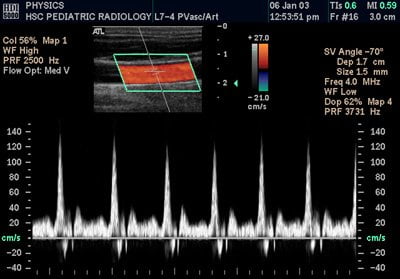

Finalmente, es posible obtener más información aún a partir de la onda reflejada si, además de medir el tiempo que tarda en volver y la intensidad, se registra la frecuencia con la que vuelve. La cuestión aquí está en el efecto Doppler. Una vez más, no puedo entrar a discutir este fenómeno en detalle en este artículo, pero consiste en la variación de la frecuencia de una onda cuando quien la emite y tú os movéis uno hacia el otro, o al revés.

Bien, este fenómeno es de gran utilidad al utilizarlo en ecografía: así es posible saber si el objeto en el que ha rebotado la onda ultrasónica se mueve hacia el transductor, se aleja de él, o ninguna de las dos cosas, además de medir su velocidad con mucha exactitud. ¿Para qué diablos sirve esto dentro del cuerpo? Para observar la velocidad de la sangre, por ejemplo, con lo que la imagen del sistema cardiovascular no sólo muestra su estructura, sino el flujo sanguíneo.